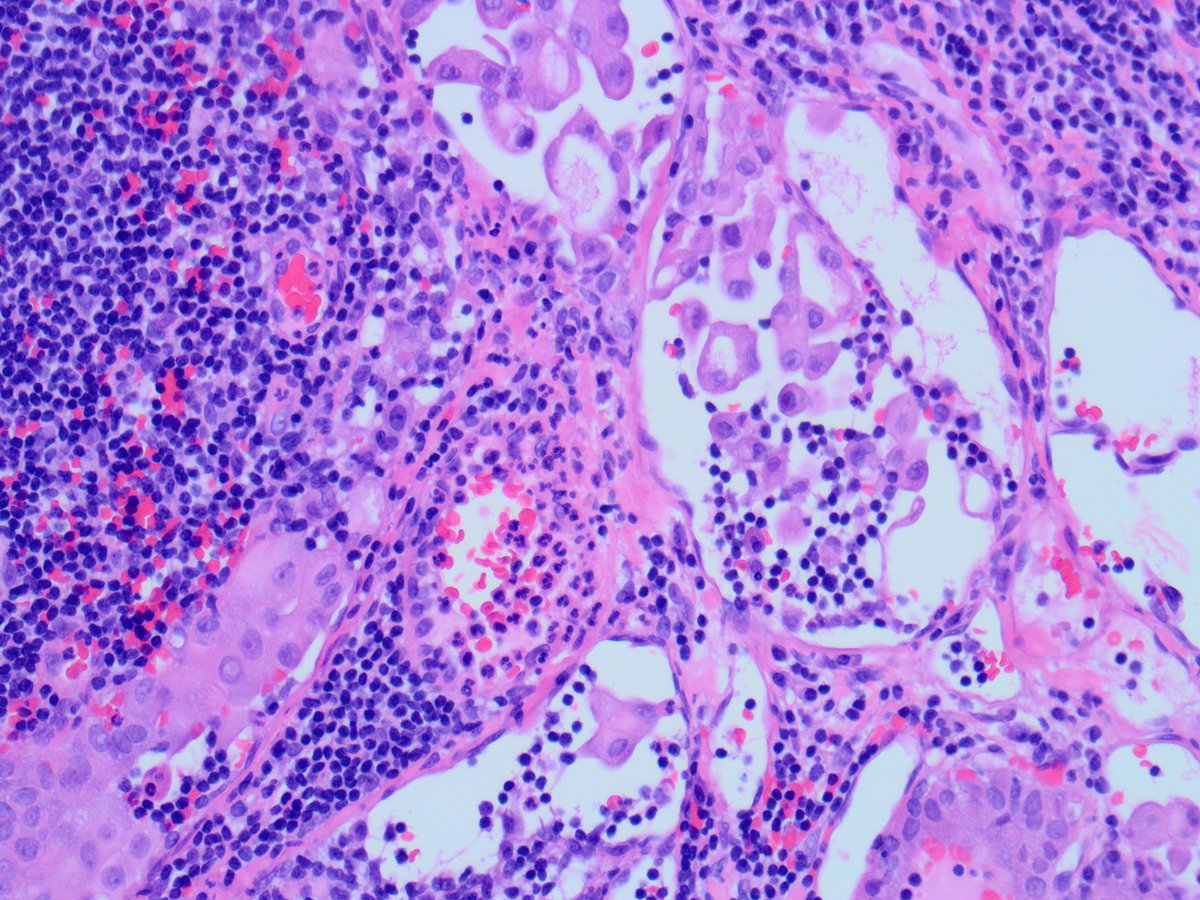

Case of the Week, submitted by our very own Dr. Huma Fatima. A 45-year-old man with a history of PTC, tall cell variant (PT3b N1a M0), s/p total thyroidectomy, central neck lymph node excision and radioactive iodine therapy, presents with new neck mass.

Some cells show tall cell morphology and rare intranuclear pseudoinclusions ("soap-bubble" appearance). These features match those seen in a previously excised cervical lymph node, consistent with metastatic tall cell variant of papillary thyroid carcinoma (PTC).

Although the sample was described as a neck mass, the presence of scattered lymphocytes suggests it is a lymph node aspirate. Cytologic features include clusters of large epithelioid cells with moderate cytoplasm and tapered tails, and atypical cells with granular cytoplasm.

Diagnostic features include: Increased tall tumor cells, especially at the periphery of clusters Granular cytoplasm with distinct borders Cytoplasmic tails and cuffs Occasional intranuclear pseudoinclusions, which are specific when present.

Tall cell variant of PTC is a more aggressive subtype of the most common thyroid malignancy, with higher recurrence risk than classic PTC. Preoperative or cytologic recognition is important for treatment planning.

The patient received radioactive iodine but no radiotherapy, and iodine does not induce radiotherapy-like cytologic changes. The cytomorphology strongly supports tall cell variant of PTC, with metastasis to a cervical lymph node, being the most likely diagnosis.

Despite the tissue culture-like appearance that might mimic reactive fibroblasts, the clinical setting, nuclear pleomorphism, cellular aggregates, and epithelioid cells in a lymphoid background support a diagnosis of metastasis over a reparative process.